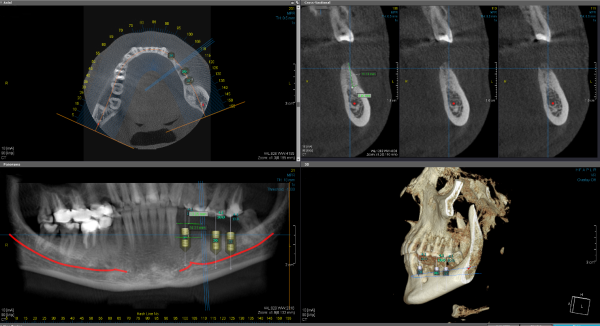

3 Boyutlu Tomografi ve Diğer Görüntülerin İncelenmesi

Öncelikle hastalarımızdan yakın zamanda çekilmiş tomografi, panoramik röntgen ve cep telefonunun arka kamerası ile bir yakınları tarafından çekilmiş, diş etlerini de inceleyebileceğimiz fotoğrafları paylaşmalarını rica ediyoruz. Hastalarımızdan paylaşacağımız “Hasta Anamnez Formu”nu doldurup ihtiyaç duyulan tedavi taleplerini ve beklentilerini iletmelerini bekliyoruz.

Ön Tedavi Planının Hazırlanması

Hekimlerimiz gönderdiğiniz medikal verileri inceleyerek operasyon için kemik yapısının uygunluğu, greft, sinüs lifting veya farklı bir tedavi gerekip gerekmeyeceğini genel sağlık durumunuzu da göz önünde bulundurarak detaylı olarak inceliyor. İmplant operasyonu için gerekli tüm unsurları göz önüne alarak ön tedavi planınızı hazırlıyoruz. Bu aşamada tedavinin yaklaşık olarak ne kadar sürede tamamlanacağı ve tahmini toplam maliyeti de sizlerle paylaşıyoruz. Tedaviyi onaylamanız durumunda en uygun randevu tarihlerini sizinle paylaşıyoruz.

Dijital Destekli Cerrahi Rehber Hazırlanması

Tedavinin başarısını artırmak ve süreci sizin için daha rahat hale getirmek için “cerrahi rehber” adı verilen bir teknoloji kullanıyoruz.

Cerrahi rehber, çene yapınıza ve ihtiyaçlarınıza özel olarak tasarlanan bir kılavuzdur. Bu rehber sayesinde, implantın yerleştirileceği alanı milimetrik hassasiyetle belirleyebiliyoruz.

Sizden aldığımız tarama ve tomografiniz eşleştirerek çene yapınıza uygun bir cerrahi rehber tasarlıyoruz. Bu süreci tamamen dijital olarak hekimlerimiz ve teknisyenlerimiz planlıyor ve 3 boyutlu yazıcılarla kliniğimizde üretiyoruz.

Cerrahi rehberi hekimlerimiz, operasyon sırasında kullanarak implantların en doğru açı ve pozisyonda yerleştirilmesini sağlıyorlar.